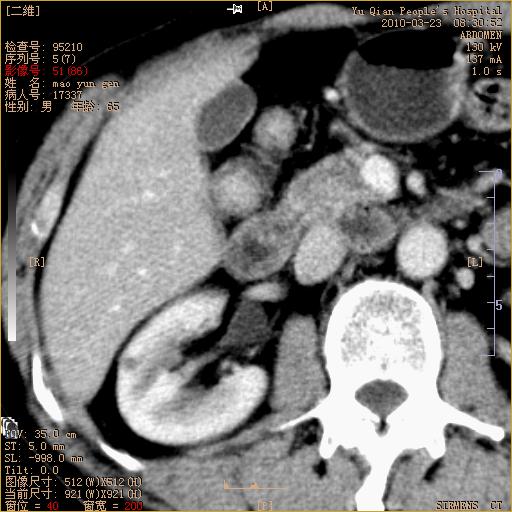

标题: CT25266:消瘦月余,前来肝部检查,请看看肠腔 [打印本页]

标题: CT25266:消瘦月余,前来肝部检查,请看看肠腔

肝区结肠占位,腺癌可考虑,建议肠镜活检。

升结肠肠壁增厚,不均强化,考虑升结肠腺癌可能性,建议肠镜检查。

1)考虑升结肠癌。2)右肾小囊肿。